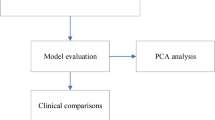

Continuous variables are presented as medians (interquartile ranges). Categorical variables are presented as counts and percentages. Baseline characteristics were compared according to cluster using the Wilcoxon signed-rank test for continuous variables and the chi-square test for categorical variables. Two clusters were created using HAC and complete linkage methods. Gower’s formula was used for calculating dissimilarities between observations. The average silhouette method was employed to determine the optimal number of clusters. The fundamental parameters considered in the cluster analysis were age (continuous), sex, DM, HT, smoking status, HL, family history, previous MI, previous revascularization, previous use of antiplatelet drugs, BB, statins and ACEis, MI pattern, PTD, DTB, TIT, KILLIP class, SBP, DBP, heart rate, WBC, PLT, creatinine, albumin, CK-MB, troponin, TC, LDL, HDL, TG, LVEF, MVD, and TIMI flow. One-month mortality risk and cluster relationships were evaluated using Kaplan‒Meier analysis, the log-rank test, and Cox proportional hazard regression models. The associations between one-month mortality risk and patient clusters were measured using hazard ratios (HRs) and 95% confidence intervals (CIs). A P value less than 0.05 was considered to indicate statistical significance. All the statistical analyses were conducted using R Studio version 3.6.3 (R Project, Vienna, Austria).

A total of 3205 STEMI patients were included in our study. The basic clinical, demographic and laboratory features of the study groups and their comparisons are summarized in Table 1. The median age of these patients was 58 years. A total of 74% of the patient population was male. Fifty-six patients were in Killip class IV at presentation. A total of 1542 of the patients presented with anterior MI. After CAG, 24 patients had a TIMI flow of 0, 72 patients had a TIMI flow of 1, and 226 patients had a TIMI flow of 2. According to the average silhouette method, the optimal number of clusters was determined to be two (Fig. 1). There were 2731 patients in cluster 1 and 474 patients in cluster 2. Patients in cluster 1 were younger than those in cluster 2. There were fewer patients with HT, diabetes, and HL and fewer smokers in cluster 1 than in cluster 2 (P < 0.001 for all). However, the rate of previous revascularization was lower in cluster 2. In cluster 2, patients used more BBs, statins and ACEIs than did patients in cluster 1. Patients in cluster 2 had higher heart rates and SBP than did those in cluster 1. Patients in cluster 2 had higher WBC counts, PLTs and creatine, CK-MB and troponin levels; additionally, they had lower albumin and Hgb levels. Patients in cluster 2 had lower LVEFs. The number of patients with Killip class 4 and TIMI 0 flow was greater in cluster 2 than in cluster (1) Anterior MI was more common in cluster (2) At the one-month follow-up, a total of 255 patients died. Among the patients who died, 147 (5.4%) were in cluster 1, while 108 (23%) were in cluster 2 (chi-square P < 0.01). Survival analysis revealed that cluster 2 had a notably elevated risk of mortality compared to cluster 1 (Fig. 2) (log-rank P < 0.001). Cox proportional hazards regression analysis was performed to evaluate the associations between one-month mortality risk and patient clusters. Cluster 2 was associated with a greater increase in the risk of death than cluster 1 (hazard ratio (HR) = 4.65, 95% CI = 3.63–5.96; P < 0.001). Even after adjusting for age and sex in the Cox proportional hazard model, the statistical significance of the association between clusters and death persisted (HR = 3.51, 95% CI = 2.71–4.54; P < 0.001).